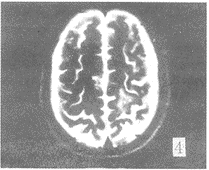

在FLAIR序列所发现81个病灶中,FSET2序列能显示的有66个,FSET2序列对病变显示率 为81.4%。FSET2序列未显示的15个病灶均位于侧脑室下、脑室旁及脑灰质区(图1,2) 。位 于脑室下的病灶,T2像未能显示。而位于基底节区,脑白质区的病灶,FLAIR及FSET2序列都 能显示。T2加权像上,所有病灶均为高信号。但在FLAIR序列,有2个病灶为低信号,1例出 血,出血灶的低信号部份T2像未能显示。另1例是T2加权像没能显示的血管畸形远端侧枝 循环(图3,4),此例为左侧颈内动脉畸形,左顶叶侧枝循环,T2像未能显示。在T2像上没能 显示而FLAIR像显示的15个病灶中,有10例为脑梗塞、脱髓鞘病变和皮层下动脉硬化性脑病 , 病灶位于脑灰质,受脑脊液影响T2像未能显示。2例为转移瘤(图5,6),肿瘤位于脑灰质,T 2像仅见水肿影。2例为脑炎、脑膜炎(图7,8),在T2像上病灶完全被脑沟中的脑脊液所掩盖 。

图3 FLAIR像左侧颈内动脉畸形,伴左顶叶远端侧枝循环,为树枝 状低信号。FSET2像(图4)左顶叶相同部位未见树枝状低信号